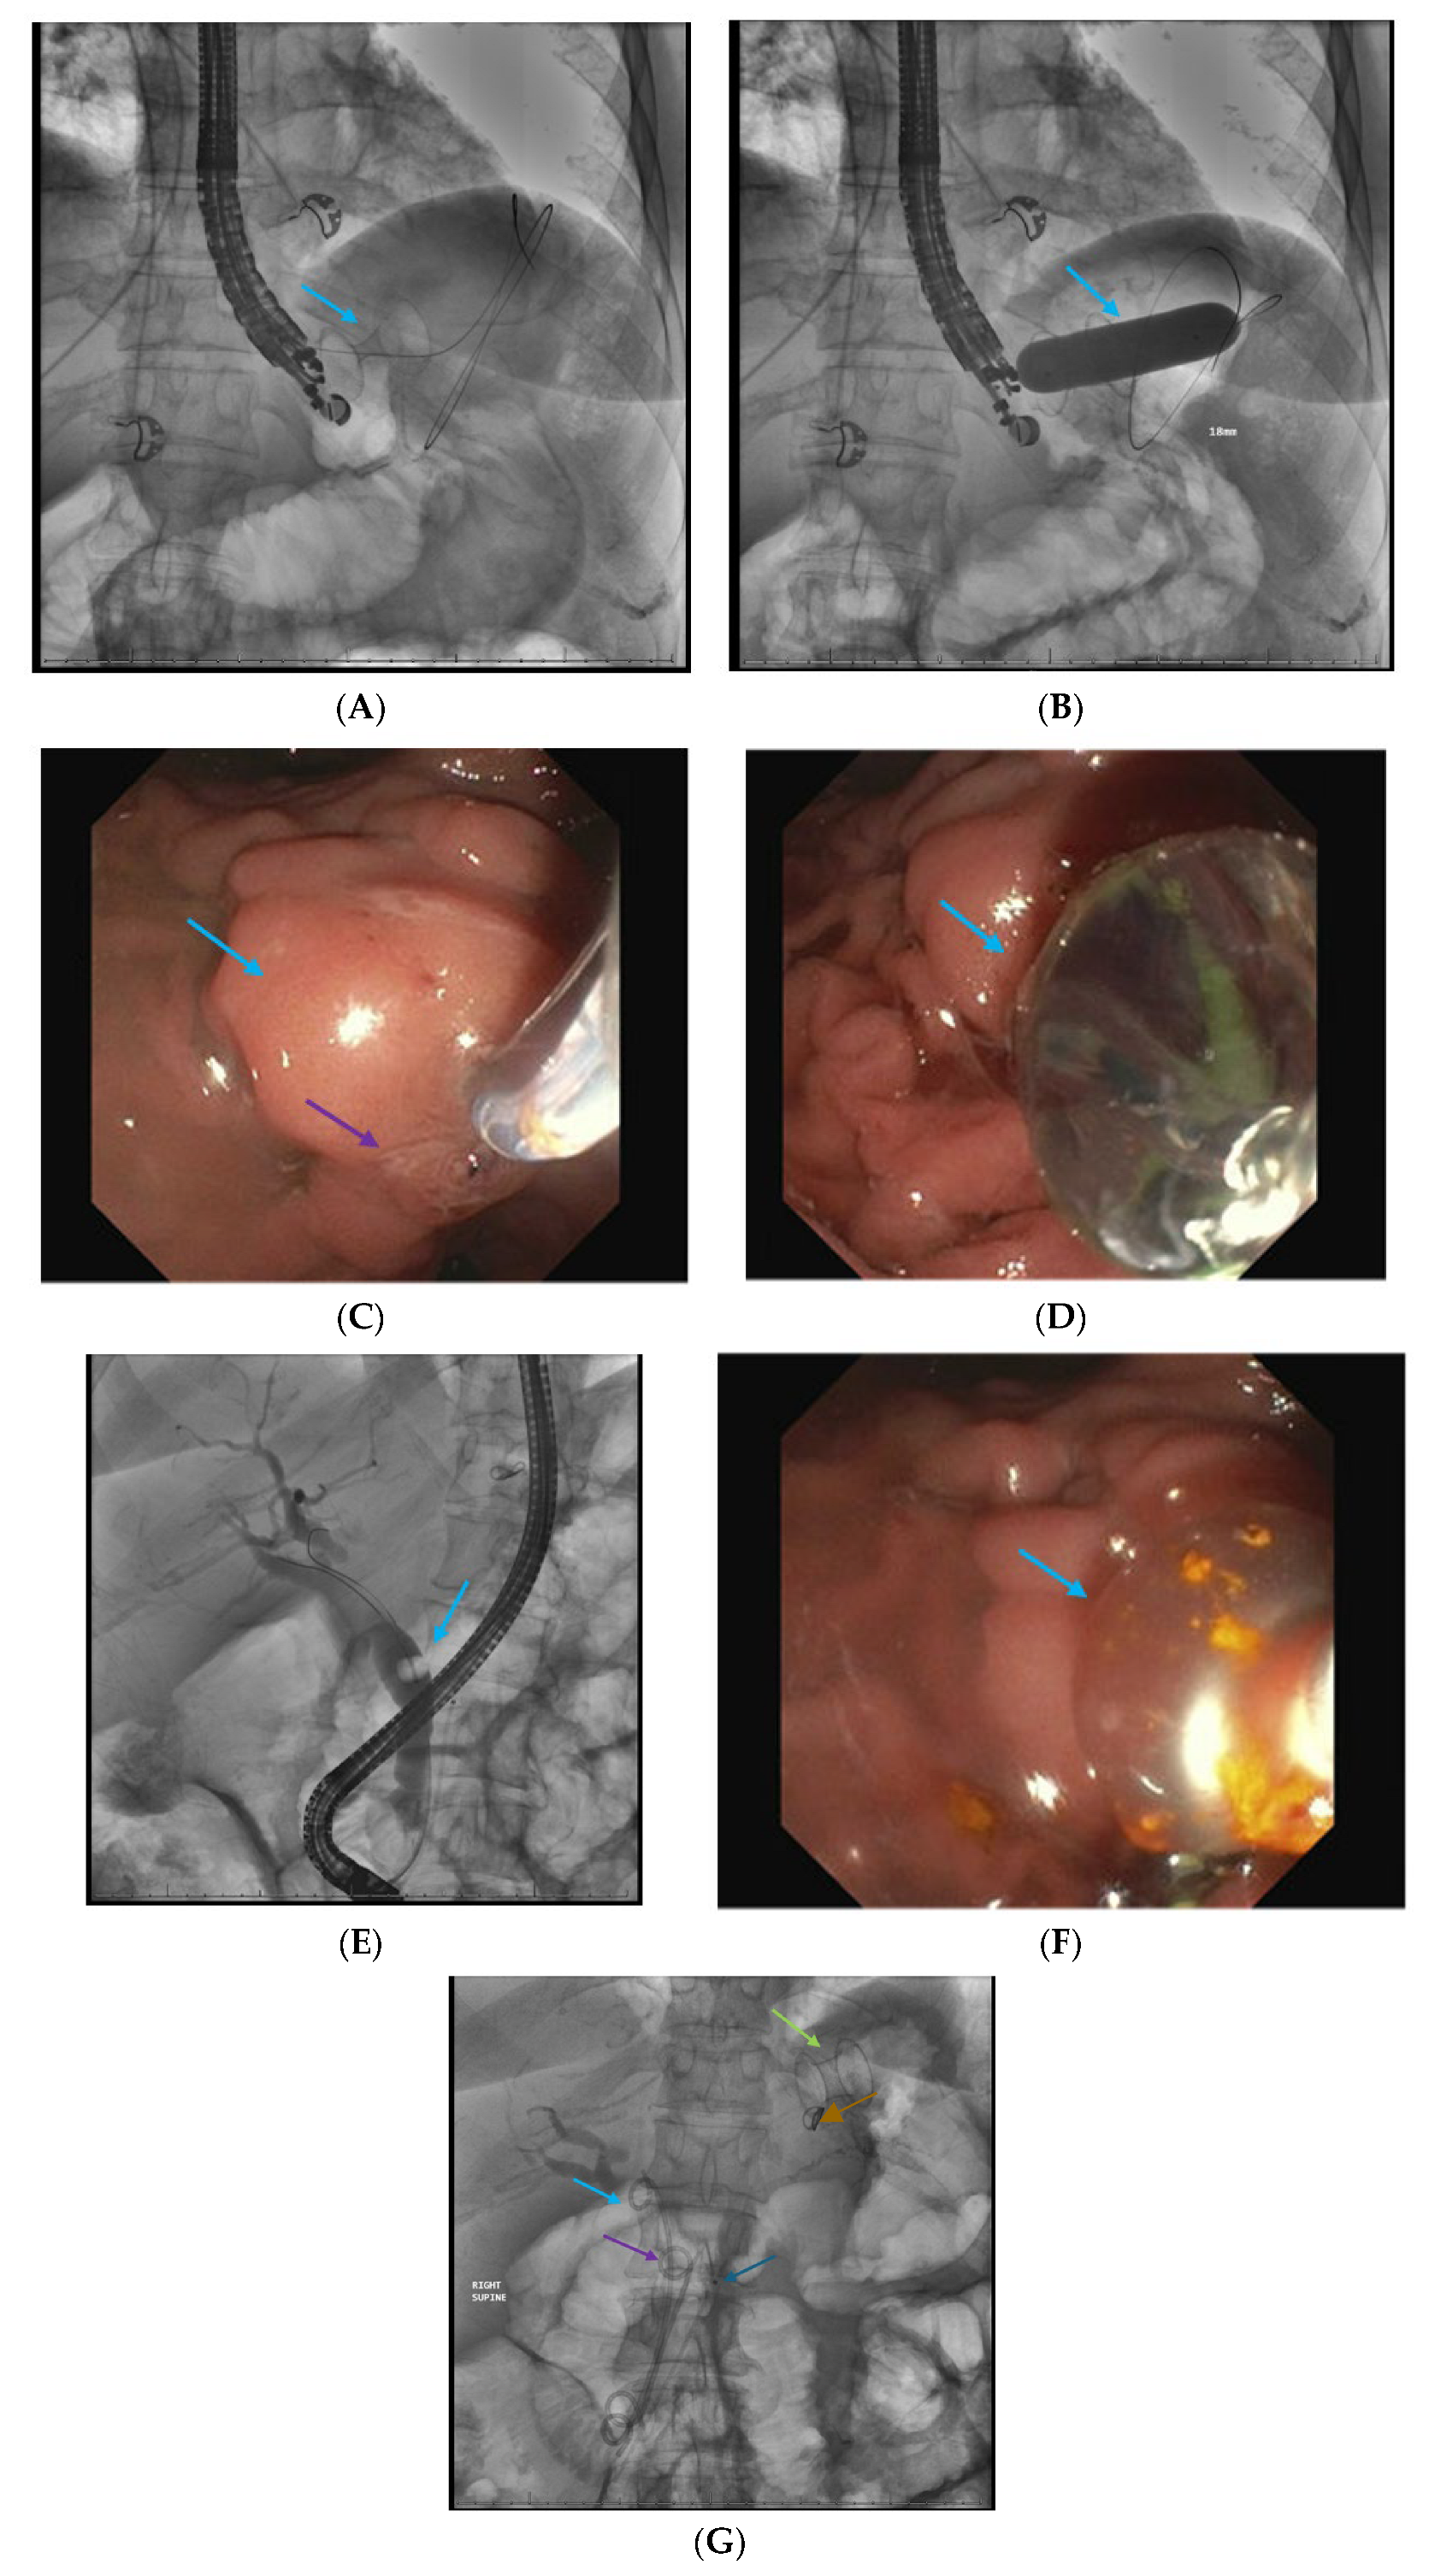

2.1. Endoscopic Retrograde Cholangiopancreatigraphy in Acute Pancreatitis

2.5. Direct Endoscopic Necrosectomy

2.6. Dual Modality Drainage

2.7. Interventional Radiology-Guided Embolization of Pseudoaneurysms

2.8. Pancreatic Fistula Treatment

2.9. Approach to Disconnected Pancreatic Duct Syndrome (DPDS) After Severe Pancreatitis

2.10. Acute on Chronic Pancreatitis—Fibrotic PD Strictures or Calculi